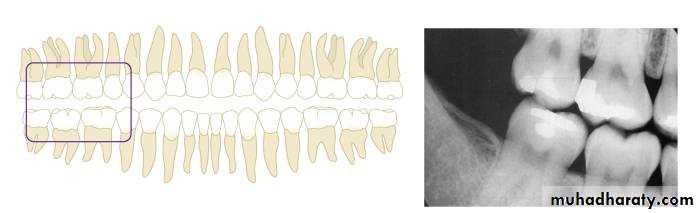

Bite-wing Radiography

• Indications:• Interproximal caries.

• Over-hang filling.

• Level of crestal bone between the teeth.

• Interproximal calculus.

• The film is placed in the mouth parallel to the crown of both upper & lower teeth.

• The film stabilized when the patient bites on the bite-wing tab or bite-wing film holder.

• The central ray of the x-ray beam is directed through the contacts of the teeth, using a +10 degree vertical angulation.

+10o vertical angulation is used to compensate for the slight bend of the upper portion of the film and the tilt of the maxillary teeth.